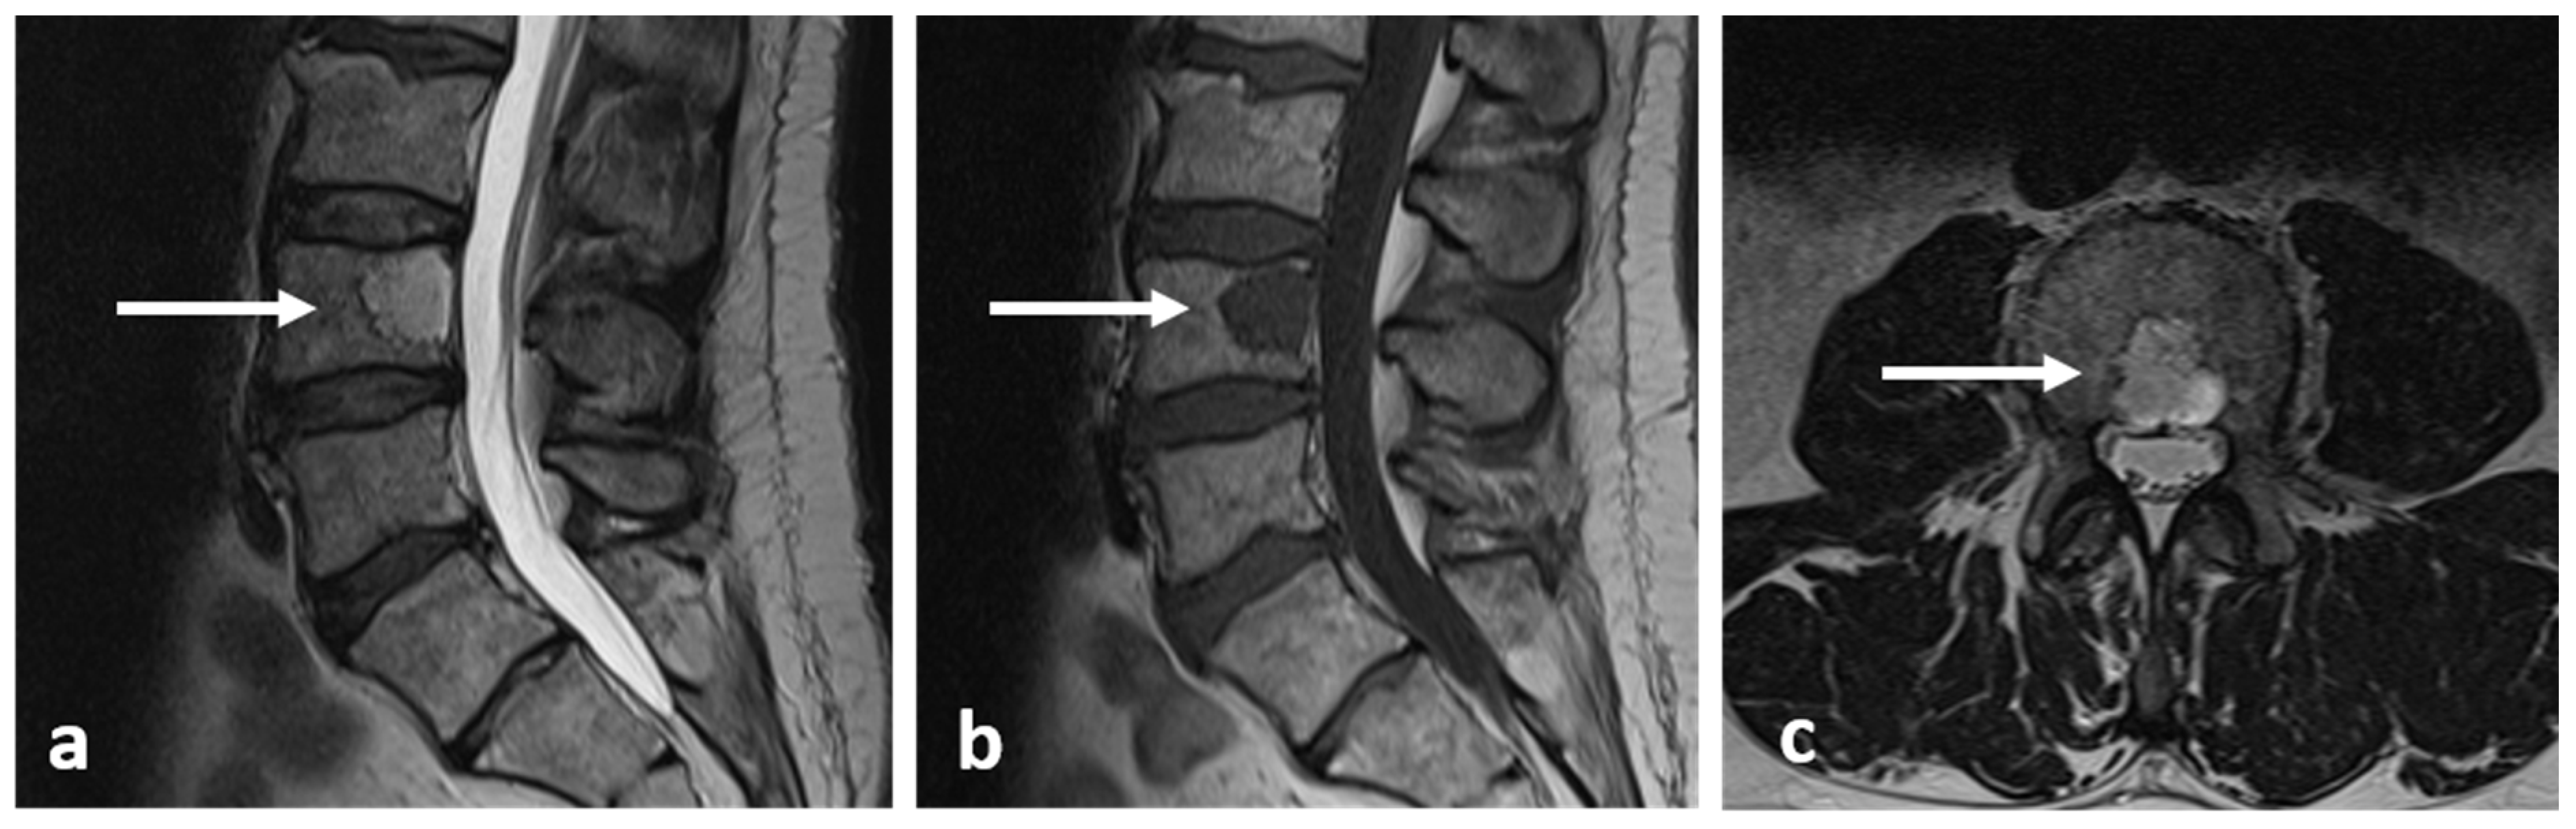

3.9. Aneurysmal Bone Cyst

- Zileli, M.; Isik, H.S.; Ogut, F.E.; Is, M.; Cagli, S.; Calli, C. Aneurysmal bone cysts of the spine. Eur. Spine J. 2013, 22, 593–601. [Google Scholar] [CrossRef]

- Girolami, M.; Caravelli, S.; Persiani, V.; Ghermandi, R.; Gasbarrini, A. Do multiple fluid-fluid levels on MRI always reveal primary benign aneurysmal bone cyst? J. Neurosurg. Sci. 2018, 62, 234–236. [Google Scholar] [CrossRef] [PubMed]

- Chan, M.S.; Wong, Y.C.; Yuen, M.K.; Lam, D. Spinal aneurysmal bone cyst causing acute cord compression without vertebral collapse: CT and MRI findings. Pediatr. Radiol. 2002, 32, 601–604. [Google Scholar] [CrossRef] [PubMed]

| Aneurysmal bone cyst | Expansile lytic lesion with internal bone septations. | Fluid—fluid levels within the cysts, high T1 signal within layering fluid content due to haemorrhage. |